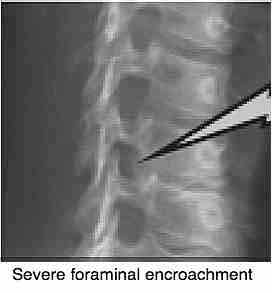

The so-called Joints of Luschka are, because of their proximity to the foramen from which the nerve exits on its way to the various parts of the body, particular susceptible to whiplash and likely to cause nerve-type symtoms in the future.